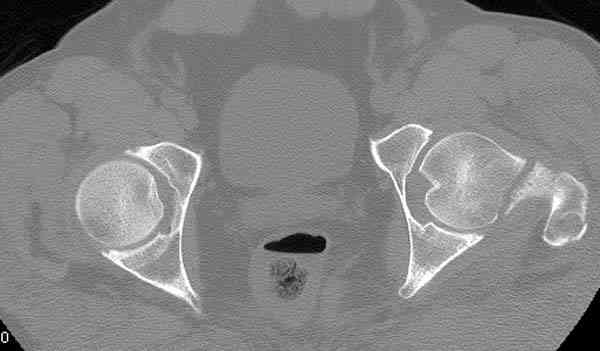

Кроме обязательных ренгенологических снимков тазобедренного сустава, при подозрении на перелом шейки рекомендуем Компьютерную Томографию.

Здесь представлены снимки больного 65 лет, поступившего с диагнозом перелом

бедра после автоаварии.

В первый же день произведено антеградное штифтованием DePuy Trochanteric Nail.

На второй день (7) обнаружен пропущенный перелом,

сделаны Компьютерная Томограмма